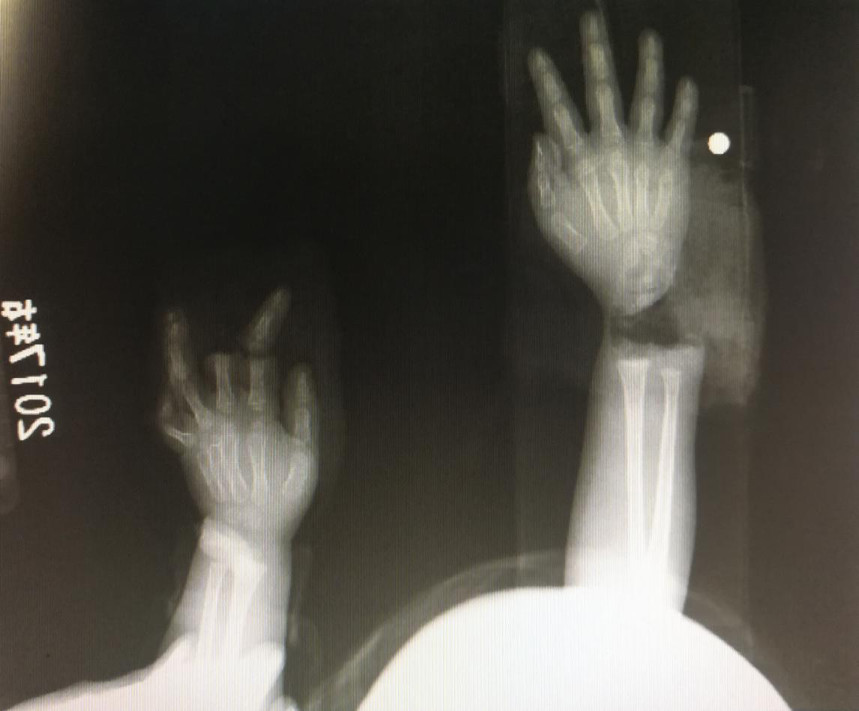

“急診在哪,急診在哪”,伴隨著一聲聲急促的問(wèn)詢(xún),一位年輕女士抱著渾身是血的小孩疾步前往急診室,懷里的小孩在疲憊與疼痛的交織下,時(shí)睡時(shí)醒。鑒于小孩的情況,急診醫(yī)生迅速安排給小孩拍了X光片,影像片結(jié)果顯示小孩左手手腕完全離斷,右手中、食指離斷,距離事發(fā)時(shí)間已經(jīng)3個(gè)多小時(shí),需盡快安排手術(shù)。

經(jīng)過(guò)長(zhǎng)達(dá)5個(gè)多小時(shí)的手術(shù),小宇(化名)終于被送出了手術(shù)室,離斷的手腕和手指均已完成再植,但關(guān)于斷指的存活與否還需要經(jīng)過(guò)一個(gè)十天的觀(guān)察期。小宇的主治醫(yī)生是長(zhǎng)沙年輪骨科醫(yī)院手足外科馬思成醫(yī)生,據(jù)馬醫(yī)生介紹,小宇受傷情況比較嚴(yán)重,失血過(guò)多,而且兩個(gè)手都存在完全離斷的情況,手術(shù)時(shí)安排了兩組醫(yī)生同時(shí)進(jìn)行,整個(gè)手術(shù)過(guò)程比較順利,目前小宇還處于觀(guān)察期。